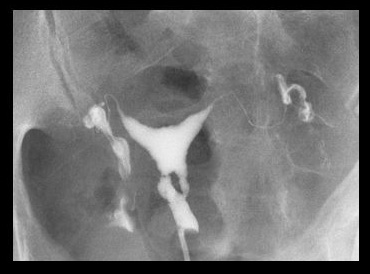

Asherman's syndrome can be diagnosed by transvaginal ultrasound (may lack typical trilaminar appearance of endometrial echo found during normal proliferative phase); however, sonohysterography or hysterosalpingography are typically the initial tests. Hysteroscopy remains the gold standard for diagnosis.[Figure caption and citation for the preceding image starts]: Lower uterine segment in patient with Asherman's syndrome, seen on hysterosalpingogramFrom the collection of Dr Meir Jonathon Solnik [Citation ends].